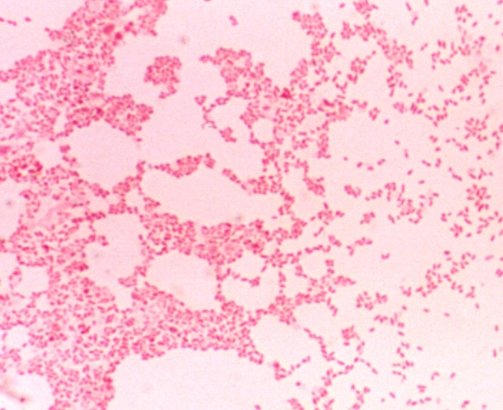

브루셀라 병이란 그램음성세균인 브루셀라속 브루셀라세균의 몇개 균종으로 발생하는 감염병으로 발열과 전신증상이 나타나게 됩니다.